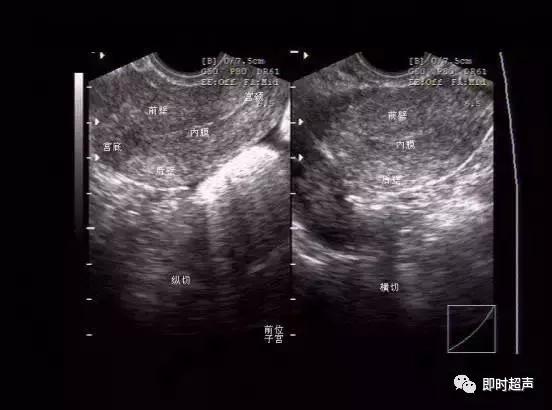

图像方位的确认

双侧卵巢的显示,与腹式超声比较,内部结构明显清晰。图片上可见数个未成熟卵泡。